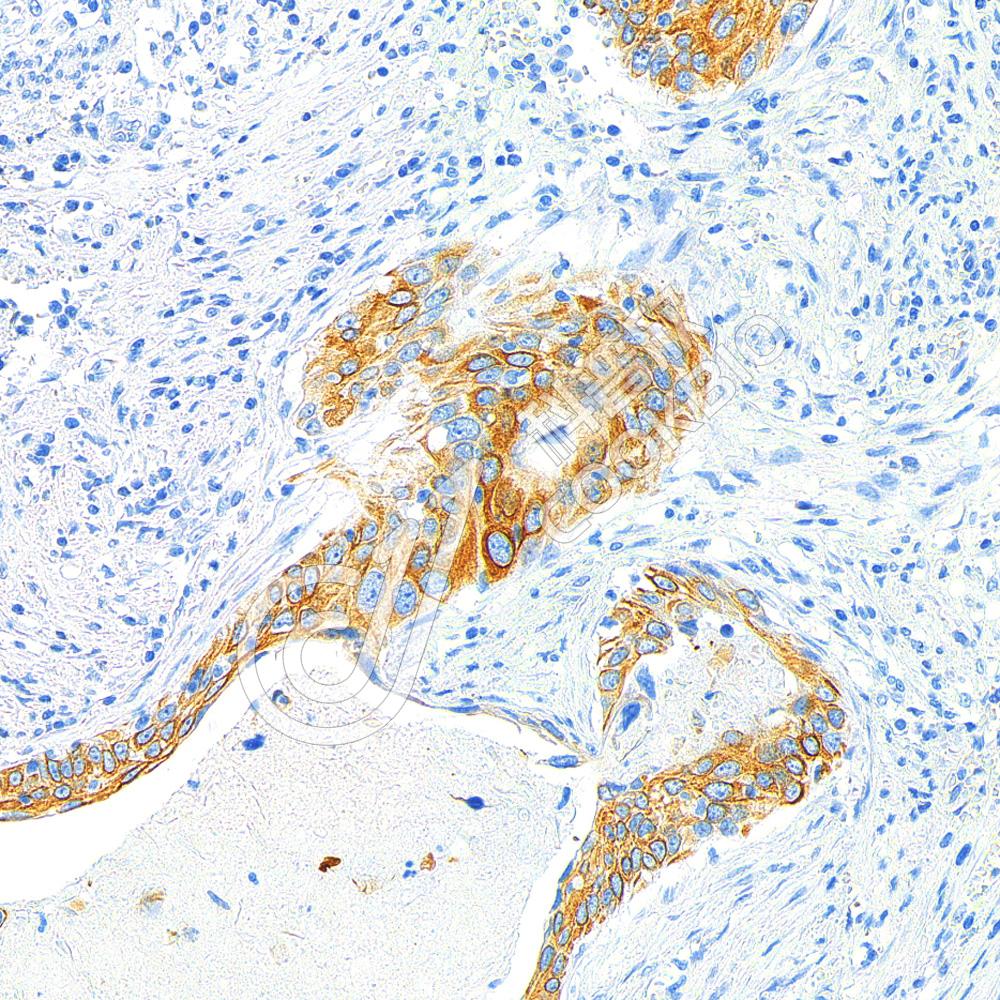

IHC检测Cytokeratin 5蛋白(货号 K1333738).

样品: 人乳腺癌, 4%多聚甲醛 (货号KSG1101) 固定12-24小时.

抗原修复: 柠檬酸抗原修复液(干粉, pH 6.0) (KSG1201), 98℃, 20分钟.

—抗: 1: 2000稀释, 4℃ 孵育过夜.

二抗: S-vision免疫组化多聚二抗(山羊抗兔),即用型 (货号KB3906), 室温孵育20分钟.